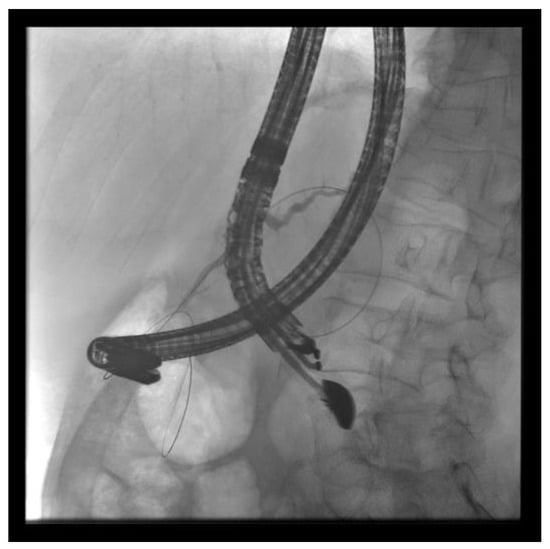

(A) EUS-ERP rendezvous technique: If the wire can be passed through the papilla and the papilla is accessible with the endoscope, a duodenoscope is employed. The guidewire is then grasped with forceps and pulled out, enabling subsequent conventional ERP with endoscopic papillary balloon dilation (EPBD) and stent placement (Figure 3 and Figure 4).

Figure 3. EUS puncture with a 19-G needle tangentially toward the papilla; the wire is passed out of the papilla via a ring knife, followed by device change of the duodenoscope.

Figure 4. After the device change, the wire is grasped with forceps and passed out, followed by a conventional ERP with stent placement (red arrow).